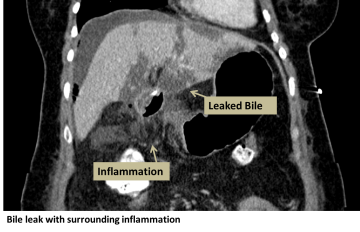

A biliary leak occurs when bile leaks out of any of the ducts that transport bile to the small intestine. Bile is made in the liver and secreted to help digest fats. Bile is made in the liver, stored in the gallbladder, and emptied into the small intestine via the common hepatic, cystic, and common bile ducts. When bile leaks out of the bile ducts, the surrounding area becomes painfully inflamed and can get infected.

- Abdominal CT scan